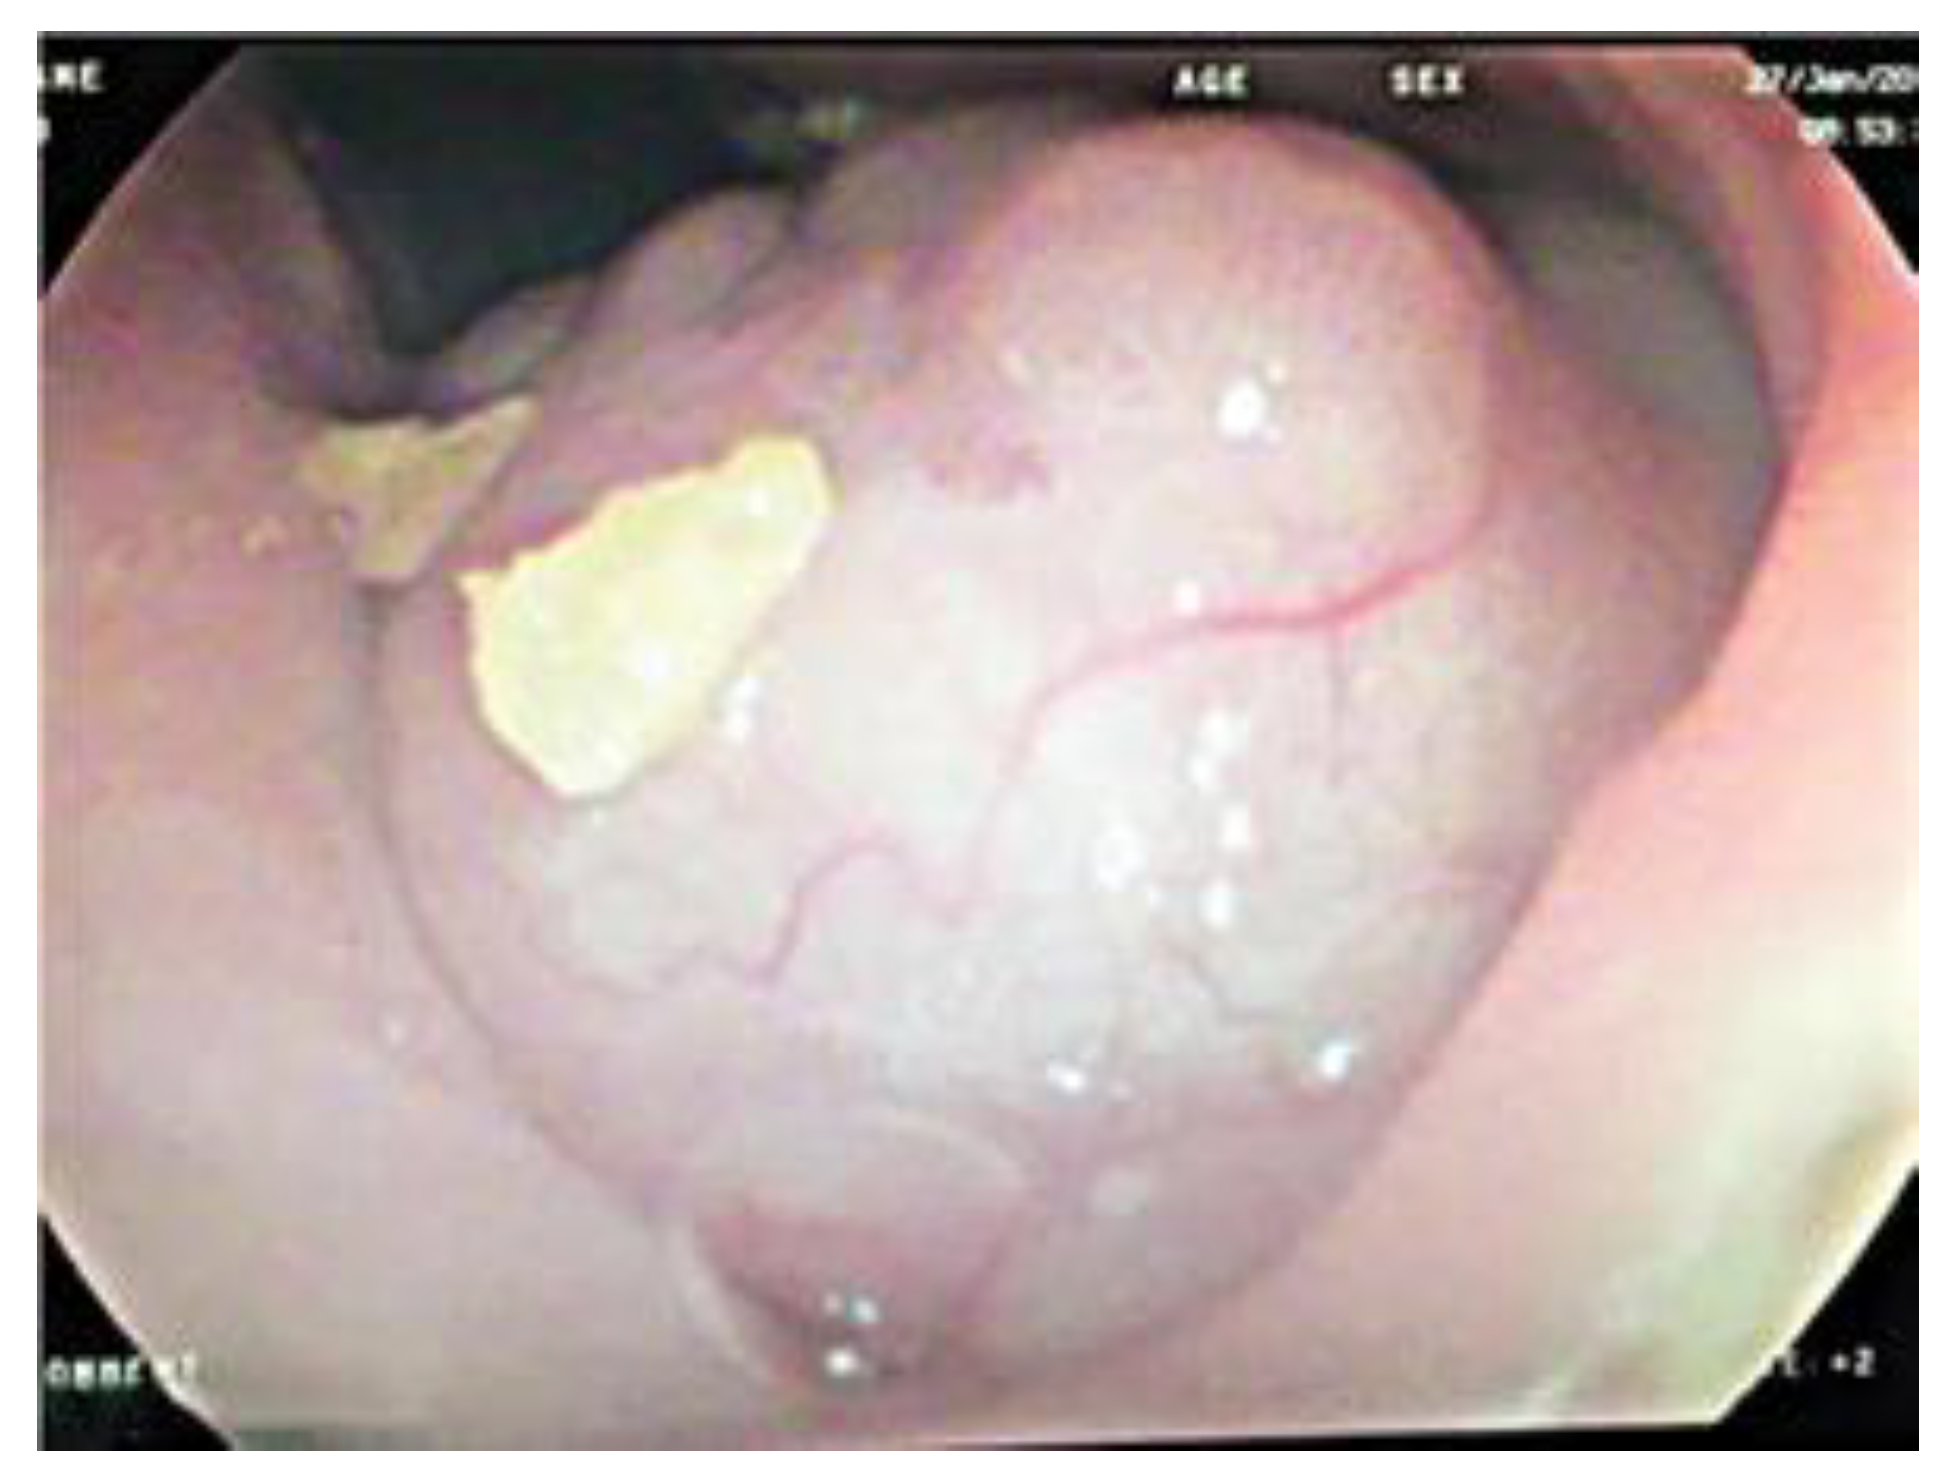

A Pedunculated Esophageal Chondromatous Hamartoma in a Child

Case Report